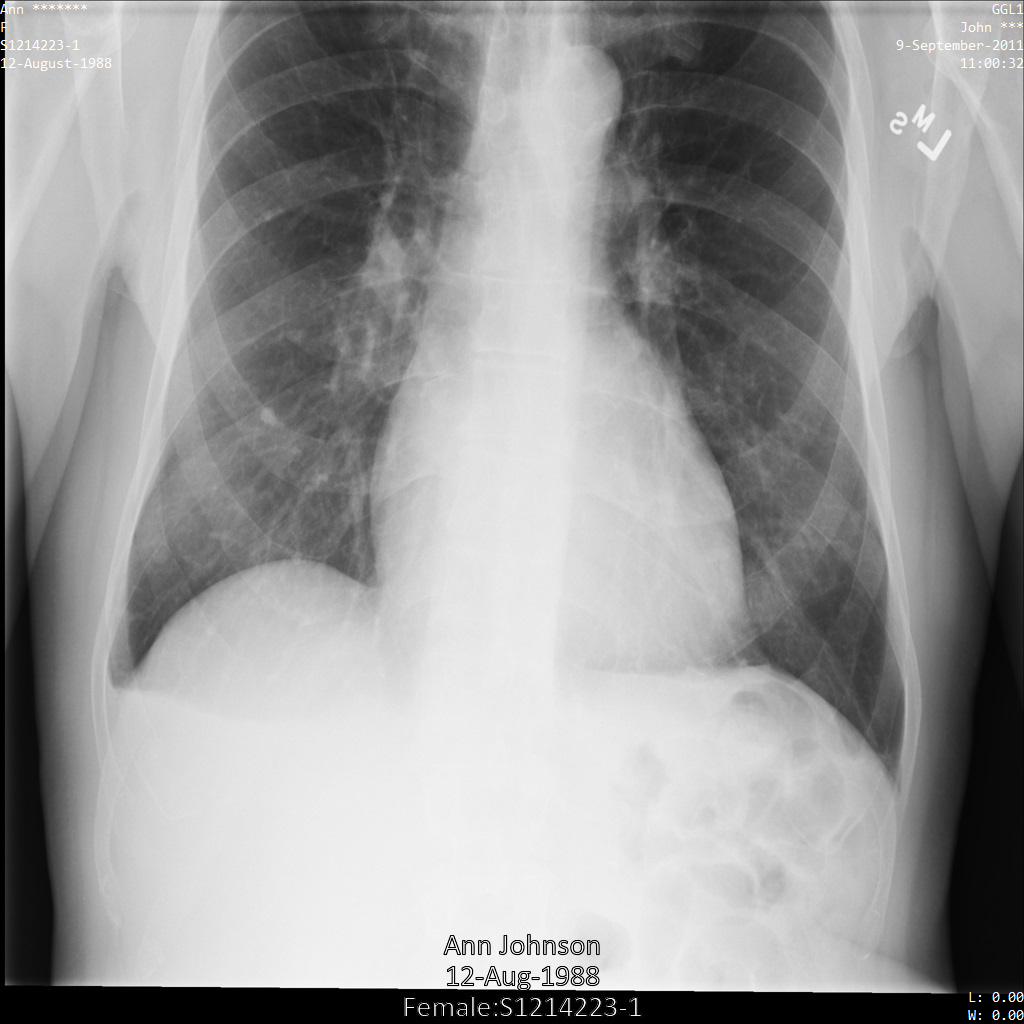

Después de enviar la imagen a la API de Cloud Healthcare mediante la opción REDACT_SENSITIVE_TEXT, la imagen aparece de la siguiente manera:

Puedes ver que ocurrió lo siguiente:

- Se ocultó el elemento

PERSON_NAMEen la esquina inferior izquierda de la imagen - Se ocultó el elemento

DATEen la esquina inferior izquierda de la imagen

El sexo del paciente no se ocultó porque no se considera texto sensible de acuerdo con los Infotipos de DICOM predeterminados.